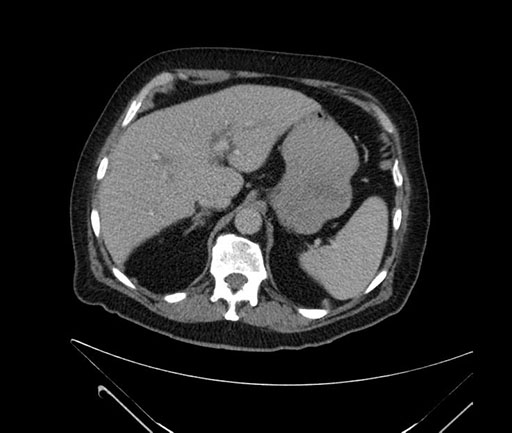

Axial - 3 months prior